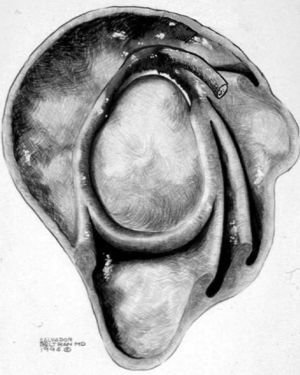

Lesión de Perthes

La lesión de Perthes es similar a la de Bankart, con la excepción de que no existe rotura capsuloperióstica, aunque el periostio puede estar separado del borde anterior del margen glenoideo (fig. 10). Esta lesión puede ser difícil de visualizar, incluso con artrorresonancia, a menos que se obtengan imágenes con la posición de abducción y rotación externa (ABER). En un estudio de 10 casos, verificados quirúrgicamente, Wisher et al17 comprobaron que el 50% de las lesiones de Perthes sólo podían visualizarse en la posición de ABER.

Fig. 10.--Lesión de Perthes. Artrorresonancia T1 con saturación grasa en posición ABER (abducción y rotación externa), donde se observa un arrancamiento parcial del labio glenoideo (flecha) con conservación de la unión capsuloperióstica.